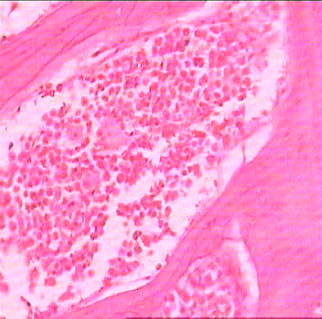

The bone marrow of Rasa Mezhugu treated rats (high/low/Middle dose) found within the central cavities of with hematopoietic tissue islands and adipose cells surrounded by vascular sinuses interspersed within a meshwork of bone (fig. 8-10). The cerebrum showed the absence of neuronal degeneration, edema and gliosis (fig. 11-13). The Cardiac muscle revealed normal appearances of the centrally arranged nucleus, connective tissue with distinct cardiac muscle fibers were well arranged (fig. 14-16). The kidney shows no glomerular or vascular injury the bowman's capsule with distinct polymorphonuclear cell nuclei with normal cells of renal cortex (fig. 17-19). The liver cells showed the normal microscopic architecture of the liver with hexagonal lobules and acini with the distinct central vein, portal triad, portal vein and hepatic artery with parenchyma cells (fig. 20-22). The lungs photos revealed that normal cytoarchitectural with predominant smooth muscle layer of the bronchi with enlargement of the alveoli and the alveoli sacs (fig. 23-25). The pancreas with normal acinar cells arranged in lobules with prominent nuclei. The islet cells are embedded within the acinar cells and surrounded by a fine capsule with normal histological structure (fig. 26-28). The spleen showed no changes congestion, hemorrhage, edema, and erosions the cells are a clear and proper arrangement (fig. 29-31). Photomicrograph of stomach mucosal layer has shown normal cells with distinct mucosa, submucosa, muscle layers and serosal layers showing normal architecture (fig. 32-34). The tests of rat’s revealed normal architecture with normal germinal epithelium, fully mature sperms filled the lumen of seminiferous tubules with tubular epithelium cells, absences of vascular congestion/interstitial edema and degenerated cells (fig. 35-37).

| Fig. 8: Histopathology slide photos of Rasa Mezhugu-High dose treated animals’ Brain | Fig. 9: Histopathology slide photos of Rasa Mezhugu-Low dose treated animals’ Brain |

| Fig. 10: Histopathology slide photos of Rasa Mezhugu-High dose treated animals’ heart | Fig. 11: Histopathology slide photos of Rasa Mezhugu-Low dose treated animals’ heart | Fig. 12: Histopathology slide photos of Rasa Mezhugu-Middle dose treated animals’ heart |